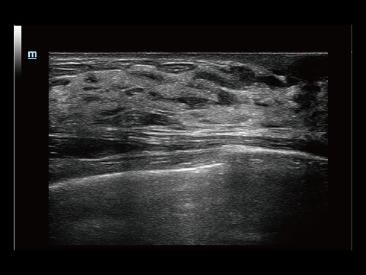

Desde que se fundó la compa?ía, Mindray ha explorado incansablemente nuevas formas de mejorar la confiabilidad del diagnóstico. Con la revolucionaria tecnología de ZONE Sonography?, la nueva plataforma ZST+ de Resona?7 lleva la calidad de la imagen por ecografía a un nivel superior mediante el procesamiento de datos de canal y la adquisición de zona.

Además de la calidad de imagen de primer nivel, Resona?7 también mejora las capacidades de investigación clínica con el revolucionario V?Flow para la evaluación hemodinámica vascular y con la adquisición de planos más inteligente a partir de conjuntos de datos 3D para el diagnóstico del SNC fetal. Al combinar el funcionamiento multitáctil basado en gestos más intuitivo y todas las características clínicas esenciales, Resona?7 realmente lidera las novedades en innovación de ecografías.